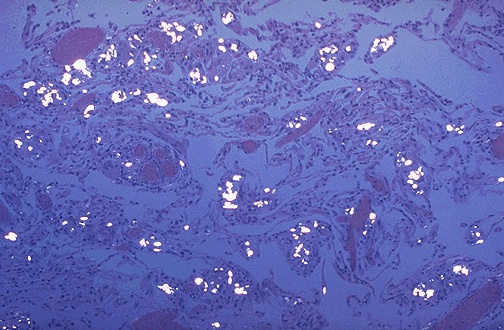

| Bright white collections of polarizable crystals are seen here, but are diffuse and centered around vascular spaces. This is the lung of a patient with a long history of intravenous drug use. Only about 1% of such persons get a significant degree of pulmonary fibrosis. The crystals represent talc that is used to to dilute the injected drug. |